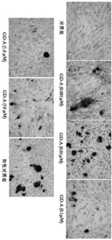

图7为GD-A诱导人间充质干细胞向成骨细胞分化过程成骨细胞标志物碱性磷酸酶的检测结果图:其中A表示成骨细胞标志物碱性磷酸酶的表达;B表示成骨细胞标志物碱性磷酸酶的酶活;Figure 7 is a graph showing the detection results of the osteoblast marker alkaline phosphatase during the differentiation of human mesenchymal stem cells into osteoblasts induced by GD-A: A represents the expression of the osteoblast marker alkaline phosphatase; B represents the osteoblast marker The enzymatic activity of the cellular marker alkaline phosphatase;

图8为GD-A诱导人间充质干细胞向成骨细胞分化过程细胞形态变化图;Fig. 8 is a graph showing changes in cell morphology during the differentiation of human mesenchymal stem cells into osteoblasts induced by GD-A;

用不同剂量GD-A(0.001μM,0.01μM,0.1μM,1.0μM和10μM)添加到人间充质干细胞中,在加药后第17天,采用茜素红染色,检测成骨细胞的另一标志特征形成钙化结节。如图8所示,对照组染色前的细胞仍然呈梭形,细胞没有形成不透明矿化钙结节,而阳性对照组及GD-A给药组染色前细胞已变成卵圆形到多边形,细胞汇合成鹅卵石状,形成了不透明的矿化钙结节。最后采用茜素红染色的结果如图9所示,并与类似常规成骨诱导阳性对照组,GD-A给药组形成了数量不等的红色矿化钙结节,尤其是0.01μM剂量GD-A组,有大量红色的矿化钙化结节。Different doses of GD-A (0.001 μM, 0.01 μM, 0.1 μM, 1.0 μM and 10 μM) were added to human mesenchymal stem cells. On the 17th day after dosing, alizarin red staining was used to detect another increase in osteoblasts. The hallmark feature is the formation of calcified nodules. As shown in Figure 8, the cells in the control group were still spindle-shaped before staining, and the cells did not form opaque mineralized calcium nodules, while the cells in the positive control group and GD-A administration group had become oval to polygonal before staining. The cells coalesced into cobblestones, forming opaque nodules of mineralized calcium. Finally, the results of alizarin red staining are shown in Figure 9. Similar to the positive control group of conventional osteogenic induction, the GD-A administration group formed different numbers of red mineralized calcium nodules, especially the 0.01 μM dose of GD. - Group A with numerous red mineralized calcified nodules.